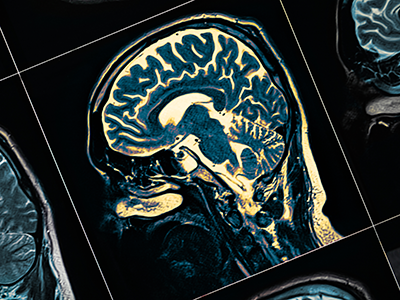

L. Gilbert Vézina, MD, is a professor of radiology and pediatrics at George Washington University and the director of the Neuroradiology Program at Children's National Hospital. He is a graduate of McGill Medical School and completed radiology and neuroradiology training at Massachusetts General Hospital. Dr. Vézina is a fellow of the American College of Radiology and a past president of the American Society of Pediatric Neuroradiology (ASPNR). He has more than 200 journal and literary publications on pediatric neuroradiology. His clinical and research interests include fetal/neonatal imaging and imaging of patients with brain tumors, epilepsy, congenital anomalies, phacomatoses, traumatic brain injuries and head and neck disorders. He was awarded the Gold Medal by the ASPNR in 2020, the society's most distinguished honor, in recognition of his exceptional service and achievements.